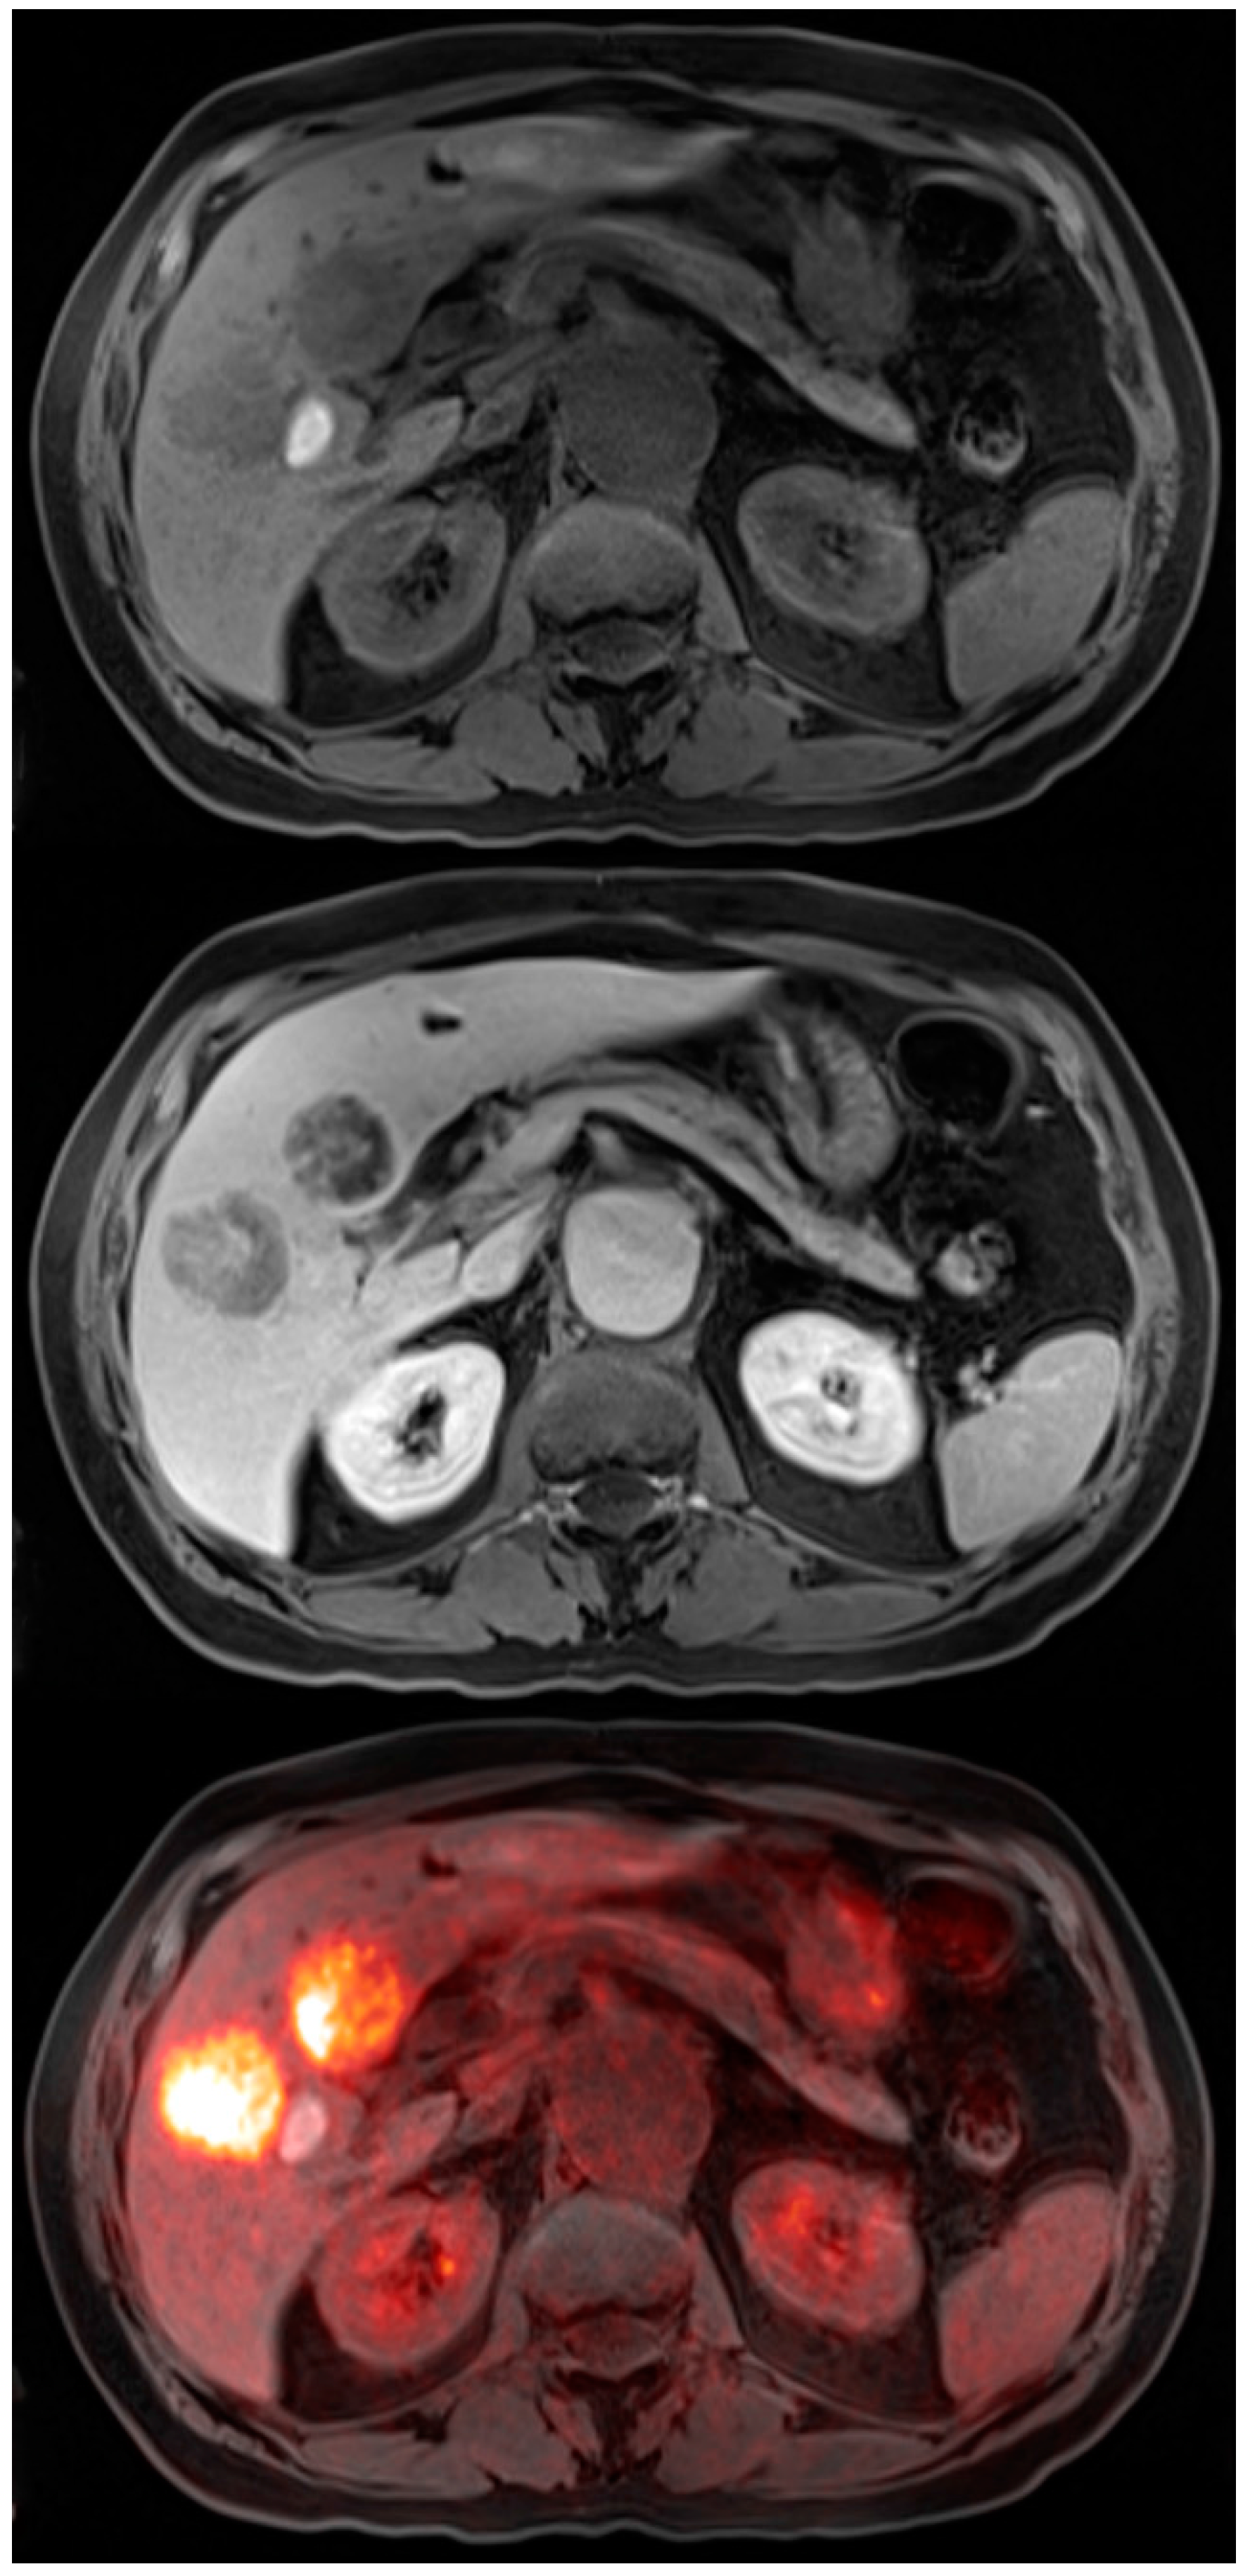

CT has the ability to assess for locoregional involvement, as well as, distant metastases. It has limitations in T staging but can provide anatomic information of metastatic lymph nodes based on size and morphology criteria. The addition of PET imaging can detect normal size lymph nodes with cancer involvement. PET is more suitable in detecting distant metastatic disease, especially hepatic metastases [22,23]. In recent literature, MRI has shown good diagnostic performance in both tumor and lymph node staging with better results with newer sequences [24]. PET-MRI imaging using newer MRI sequences has a potential for better tumor, nodal, and distant metastatic involvement. Early MRI imaging of the stomach was difficult due to respiratory motion and bowel peristalsis. With new free breathing sequences, this problem has been mostly eliminated. Huang et al. did a meta-analysis of 439 patients for using MRI in T and N staging for gastric cancer. Pooled analysis showed the sensitivity of MRI for distinguishing T1-2 vs. T3-4 was 93% with specificity of 91% however for N staging sensitivity was 86% with specificity of only 67% [24]. Figure 2 illustrates a case of gastric cancer using PET-MRI as a staging modality. Future studies are needed to find out if PET-MRI can improve the nodal staging specificity in this disease.

Figure 2.

64-year-old female for initial staging of gastric cancer. The PET-MRI transaxial fusion image shows intense hypermetabolic activity in the gastric cancer with SUV 29.2 and a hypermetabolic enlarged gastrohepatic lymph node (top left). T1 radial vibe transaxial image with fat suppression shows the gastric cancer to be of low to isointense signal and the metastatic lesion to be hyperintense (bottom left). T2 haste transaxial image shows a hyperintense liver lesion that was not active on the PET images which is consistent with a hemangioma (top right). The PET MIP image shows the intense activity in the stomach with activity in the adjacent gastrohepatic lymph node (bottom right).